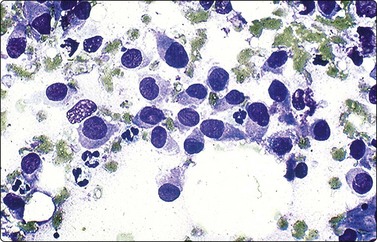

The small non-cleaved cell lymphomas such as Burkitt and non-Burkitt types, usually presents in the nonendemic form with enlargement of abdominal lymph nodes and/or visceral organs.4,45,71 Ovarian involvement may be seen in females. Aspiration smears are highly cellular and demonstrate monotonous population of singly dispersed cells with round nuclei, moderate to high nuclear to cytoplasmic ratios, coarse clumping of chromatin, and prominent nucleoli (Fig. 17.13). Multiple nucleoli are seen in Burkitt-type and single nucleoli are noted in the non-Burkitt type. Nuclear irregularities and polylobated nuclei are often seen. On Romanowsky-stained smears, numerous cytoplasmic vacuoles are seen in Burkitt lymphoma (Fig. 17.14). The vacuoles are due to the accumulation of neutral lipids, which can be stained with oil-red-O. Abundant mitotic figures and apoptosis are seen and are indicative of a tumor with extremely rapid turnover. Phagocytic histiocytes are often seen in the background.

image

Fig. 17.13 Burkitt lymphoma

Aspirates are extremely cellular, containing intermediate-sized, predominantly round nuclei with coarsely clumped chromatin and one or more prominent nucleoli (Papanicolaou, ×200).

Fig. 17.14 Burkitt lymphoma

Romanowsky-stained smears demonstrate cytoplasmic lipid vacuoles which are lost with alcohol fixation. Nuclei can be polylobated and irregular (Diff-Quik×200).